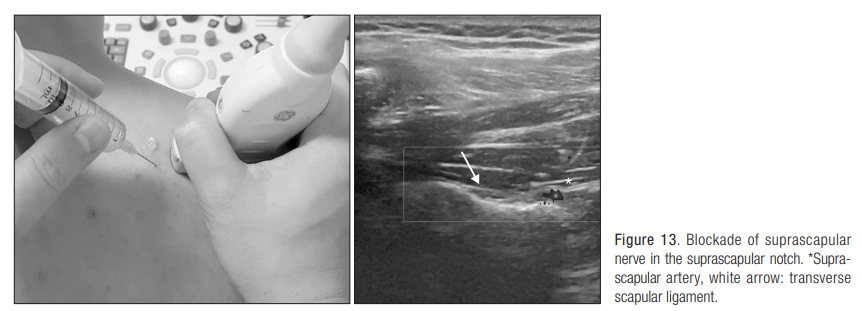

8. 상견갑 신경 차단술(suprascapular nerve block injection)

상견갑 신경의 감각 신경 분지는 견갑골과 견봉 쇄골 관절, 견관절 상부와 후면의 70%를 포함하는데, 어깨 주변부의 감각 신경 영역의 상당 부분을 차지하고 있다.

즉, 어깨 통증 발생 시 상견갑 신경이 많은 관여를 하고 있으며, 신경에 주사를 놓는 신경 차단술은 효과적인 통증 치료법으로 알려져 있다.

주사 자세 및 해부학적 구조는 다음과 같다.

1) 탐촉자를 suprascapular fossa의 외측 1/3 부위로 극상건의 주행방향으로 설정

2) 탐촉자를 이용해서 상견갑 절흔과 그 위에 있는 상견갑회인대(transverse scapular ligament)를 확인

3) doppler를 이용해서 suprascapular artery의 pulsation을 확인한 뒤, 피해서 주사

국소 마취제가 혼합된 10cc 정도의 용액을 6cm 길이의 23 게이지 주사를 이용

탐촉자와 수평된 상태로, 45도 각도로 삽입

상견갑횡인대 (transverse scapular ligament)에 needle 끝이 위치한 것을 확인한다. ligament를 통과하지 않는다.

ligament를 통과하여 절흔 안으로 needle을 위치하면 신경 손상이 가능성이 있기 때문이다.